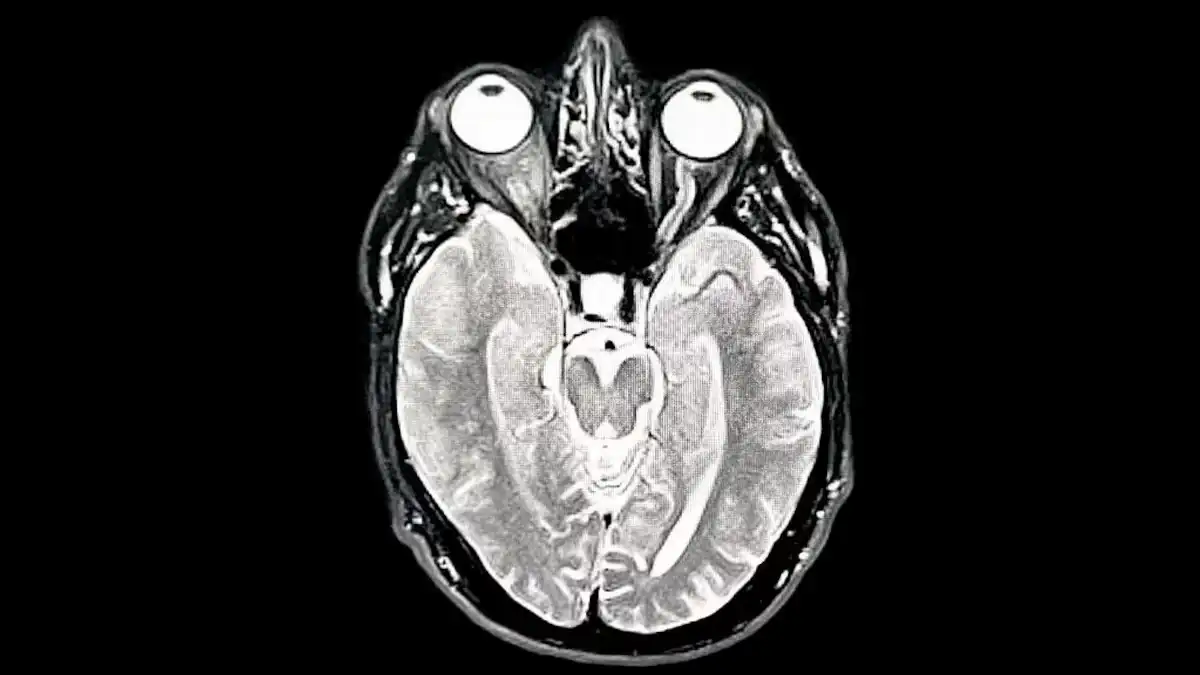

la “adolescencia del cerebro” dura mucho más de lo que imaginábamos. Tras estudiar miles de imágenes cerebrales, encontraron que las redes neuronales siguen ajustándose, optimizándose y funcionando con un nivel de flexibilidad extremo hasta pasada la treintena. Es decir, el cerebro no llega a su punto máximo de organización en la juventud temprana, sino a comienzos de los 30, justo cuando muchas personas creen haber alcanzado su etapa más estable.

El estudio propone además un mapa distinto del desarrollo cerebral: cinco momentos clave que marcan saltos importantes en cómo pensamos, aprendemos y procesamos el mundo, con hitos que coinciden con fases vitales tan reconocibles como la infancia, la adultez inicial o los primeros signos del envejecimiento. Para los investigadores, esto abre la puerta a replantear cómo entendemos la madurez mental, el riesgo de trastornos y la forma en que cambia nuestra mente a lo largo de la vida.